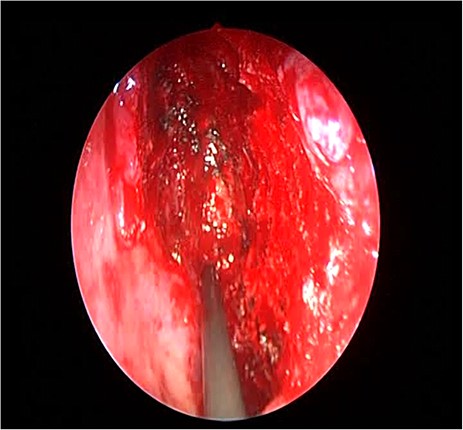

The patient underwent image-guided endoscopic endo-nasal removal (Fig. 5) of a large fibro-osseous tumor, the tumor was adherent to the orbit and skull base which was removed (Fig. 6). The resected tumor was sent to the histopathological examination, which confirmed the final diagnosis of fibrous dysplasia. The patient remained free of symptoms with no recurrence for 3 years after the resection.

Endoscopic image showing the cavity after tumor removal from the orbit and skull base.